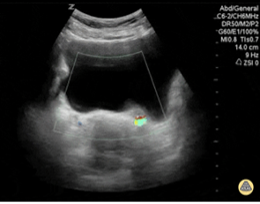

In addition to the cardiac windows, lung ultrasound (LUS) can also provide valuable indirect information about LV performance. LUS is highly sensitive to detect early or subtle increases in left ventricular end diastolic filling pressures (LVEDP) [24].

In the setting of LV systolic dysfunction or congestive heart failure, elevated LVEDP leads to pulmonary congestion, which manifests on LUS as the progressive appearance of B-lines. B-lines occur as the edema or excess extravascular lung water interact with air-filled alveoli to create a reverberation artifact. The distribution and severity of B-lines correlate with the degree of pulmonary interstitial edema or fluid overload and, by extension, can reflect deterioration in LVfx.

Integrating LUS findings with cardiac PoCUS can provide a more comprehensive assessment of LVfx.